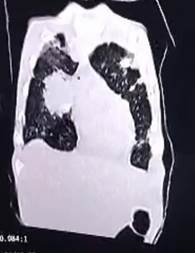

El estudio tomográfico de tórax revela lesiones infiltrativas de aspecto tumoral bilateral cerca del área de mediastino en el lado derecho y lesiones periféricas cerca del área pleural, bilateral.

Imagen 6.

Vista sagital de la tomografía computarizada que muestra lesiones parenquimatosas y periféricas